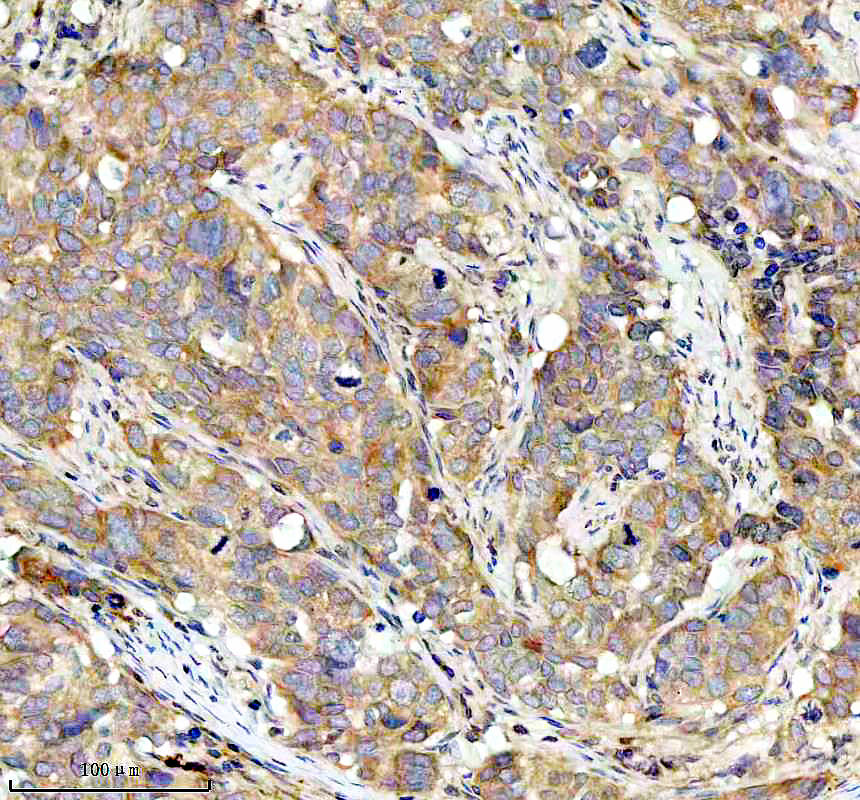

IHC analysis of BNIP3L using anti-BNIP3L antibody (BM5174) .

BNIP3L was detected in a paraffin-embedded section of human bladder cancer tissue. The tissue section was incubated with rabbit anti-BNIP3L Antibody (BM5174) at a dilution of 1:200 and developed using HRP Conjugated Rabbit IgG Super Vision Assay Kit (Catalog # SV0002) with DAB (Catalog # AR1027) as the chromogen.

IHC analysis of BNIP3L using anti-BNIP3L antibody (BM5174) .

BNIP3L was detected in a paraffin-embedded section of human bladder cancer tissue. The tissue section was incubated with rabbit anti-BNIP3L Antibody (BM5174) at a dilution of 1:200 and developed using HRP Conjugated Rabbit IgG Super Vision Assay Kit (Catalog # SV0002) with DAB (Catalog # AR1027) as the chromogen.